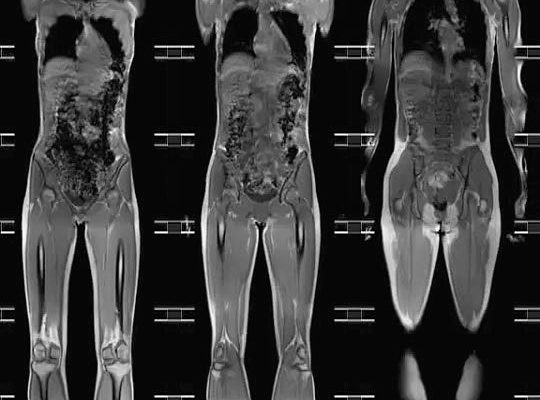

Магнитно-резонансная томография всего организма

МРТ всего тела позволяет выявить скрытые патологические процессы на ранней стадии развития. Это тест, который оценивает состояние органов и тканей организма, распознает патологию и определяет степень развития болезненного процесса.

Магнитная томография всего тела выявляет нарушения целостности органов и тканей, очаги воспаления и гнойные, врожденные и приобретенные патологические явления, скопление жидкости в полостях органов. Этот же метод используется при диагностике заболеваний коронарных артерий, изменений структуры печени, а также при мониторинге состояния аневризм аорты.